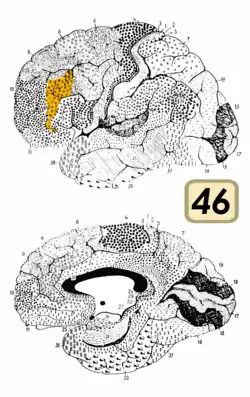

Brodmann area 46, or BA46, is part of the frontal cortex in the human brain. It is between BA10 and BA45.

BA46 is known as middle frontal area 46. In the human brain it occupies approximately the middle third of the middle frontal gyrus and the most rostral portion of the inferior frontal gyrus. Brodmann area 46 roughly corresponds with the dorsolateral prefrontal cortex (DLPFC), although the borders of area 46 are based on cytoarchitecture rather than function. The DLPFC also encompasses part of granular frontal area 9, directly adjacent on the dorsal surface of the cortex.

Cytoarchitecturally, BA46 is bounded dorsally by the granular frontal area 9, rostroventrally by the frontopolar area 10 and caudally by the triangular area 45 (Brodmann-1909). There is some discrepancy between the extent of BA8 (Brodmann-1905) and the same area as described by Walker (1940).[1]

Image

Animation. -

Frontal view. -

Lateral view.